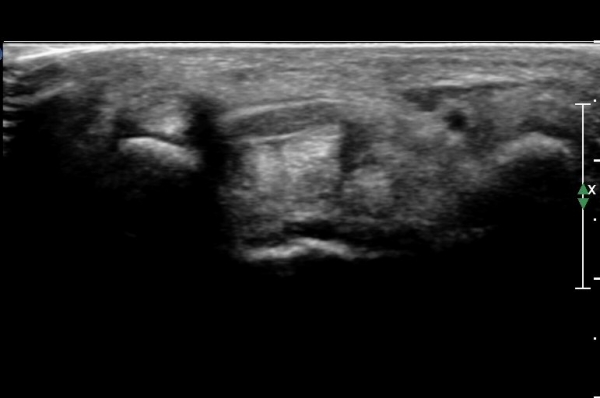

¼Õ¸ñ ºÎÀ§¿¡¼ Á¤Á߽Űæ Ⱦ´Ü¸é°Ë»ç»ó Á¤Á߽ŰÜÀÇ Àú¿¡ÄÚ ºÎÁ¾ÀÌ °üÂûµÊ(»çÁø 1).